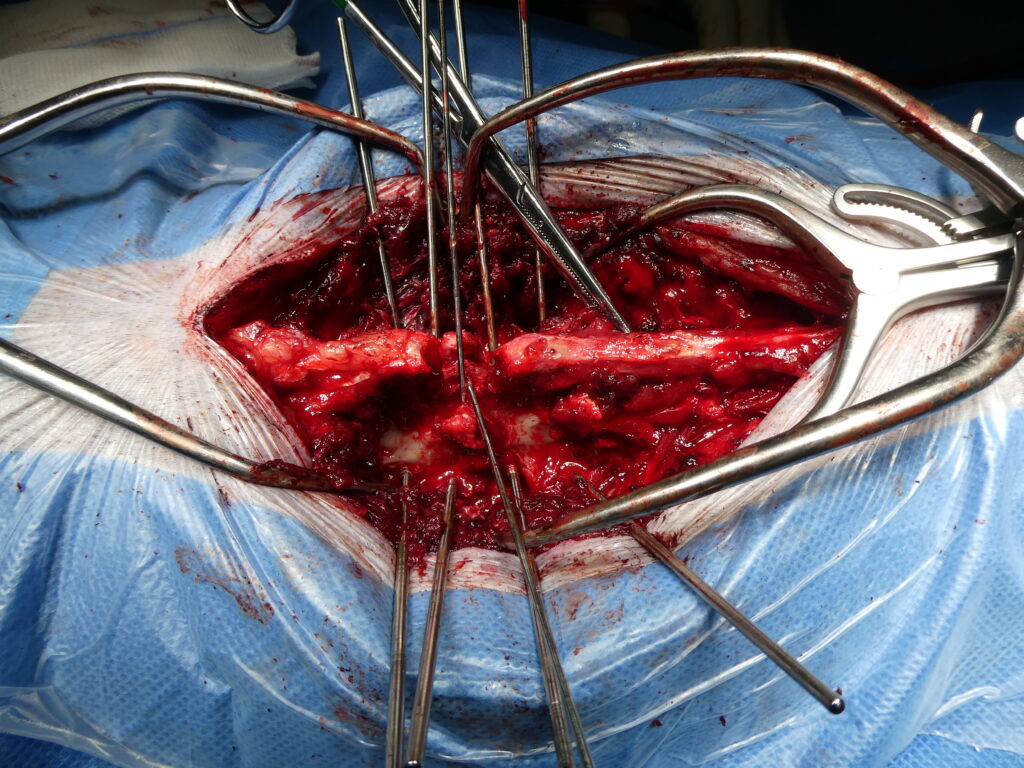

Stabilisation chirurgicale d’une luxation vertébrale T13–L1 post-traumatique chez un Berger australien.

De gauche à droite et de haut en bas, cette série d’images illustre la prise en charge chirurgicale d’une luxation vertébrale T13–L1 consécutive à un accident de la voie publique. La première image montre la reconstruction tridimensionnelle préopératoire, la flèche verte identifiant précisément le site de la luxation vertébrale. La seconde image correspond au début de l’intervention chirurgicale, avec exposition du foyer lésionnel et réduction progressive de la luxation à l’aide de daviers, sous contrôle visuel strict. La troisième image illustre l’implantation des broches de stabilisation vertébrale, un temps particulièrement délicat nécessitant un positionnement millimétrique selon des angles prédéfinis à partir de l’analyse scanner préopératoire. La quatrième image montre l’ensemble des broches une fois mises en place dans le rachis, assurant la stabilisation segmentaire. La cinquième image correspond à la phase de consolidation du montage, après recoupe des broches et mise en place d’un ciment de polyméthylméthacrylate permettant de solidariser l’ensemble. Enfin, la dernière image présente le contrôle scanner post-opératoire immédiat, confirmant le positionnement correct des implants, l’absence de pénétration dans le canal médullaire et la restauration satisfaisante de l’alignement vertébral.